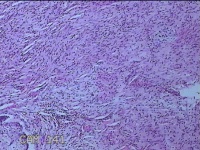

双侧肩锁关节处肿物

性别

女

年龄

30岁

临床诊断

纤维瘤病

一般病史

无

标本名称

大体所见

灰白暗红色肿物2x1.3x0.8cm两个,表面糜烂,切开肿物呈实性,切面灰白粉红色,质软。